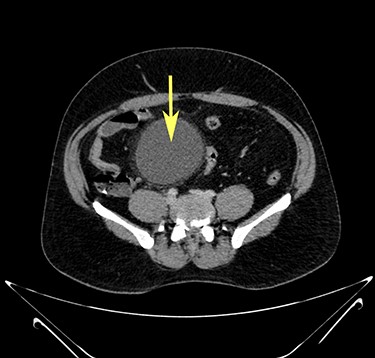

Computerized tomography showed a solitary well defined intraperitoneal cyst consisting of fluid showing low attenuation. The wall of the cyst was 1 cm thick, with no contrast enhancement. It was situated in the pelvis compressing the urinary bladder. It had no communication with either the bowel or the urinary bladder. The pancreas was normal, as also the rest of the abdominal organs. There was no ascites (Figs. 1–5). The diagnosis was a large intraperitoneal infected cyst.

Transverse section image of a contrast-enhanced CT scan of the abdomen at the level 3–3 (Fig. 1), showing a solitary cyst (arrow) with a non-enhancing wall separate from the intestines.